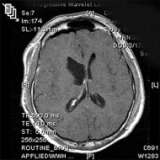

Post-operative MRI

This post-operative MRI (above) confirms image-complete removal of the tumor.